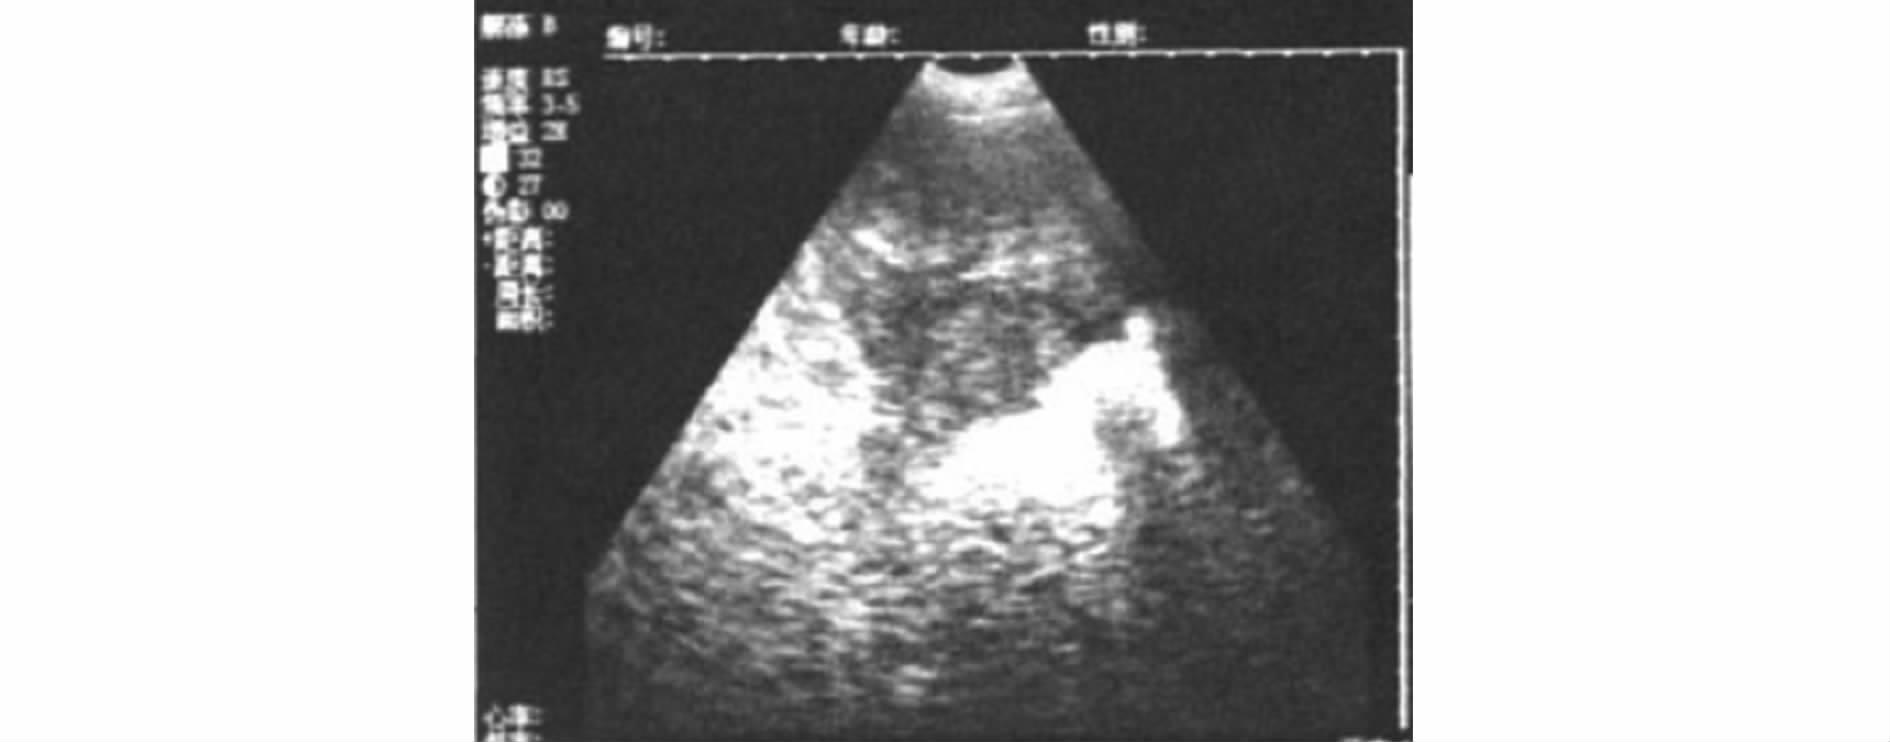

3.2.1 空怀母猪 未妊娠时子宫角位于膀胱的左右或前下方,膀胱内的积尿为液体,对超声波不产生反射,其声像图呈较规则的暗区。未妊娠时子宫角的壁对超声的反应弱,其断面的声像图呈各种不规则圆形的弱反射区(见图8)。子宫角外膜的反射也不强,要注意断面的界线,以与肠管的断面相区别,一周后复查,避免误诊。

图8 空怀母猪B超影像